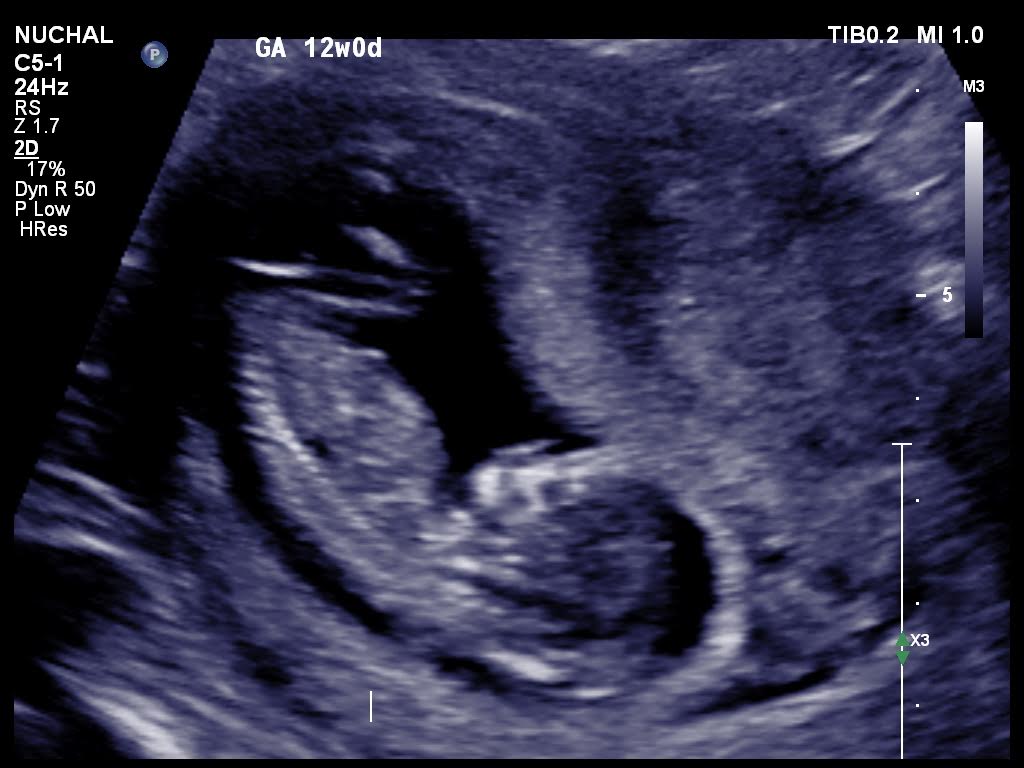

Is it possible for anybody to suggest the gender please from these 12 weeks ultrasound scans.